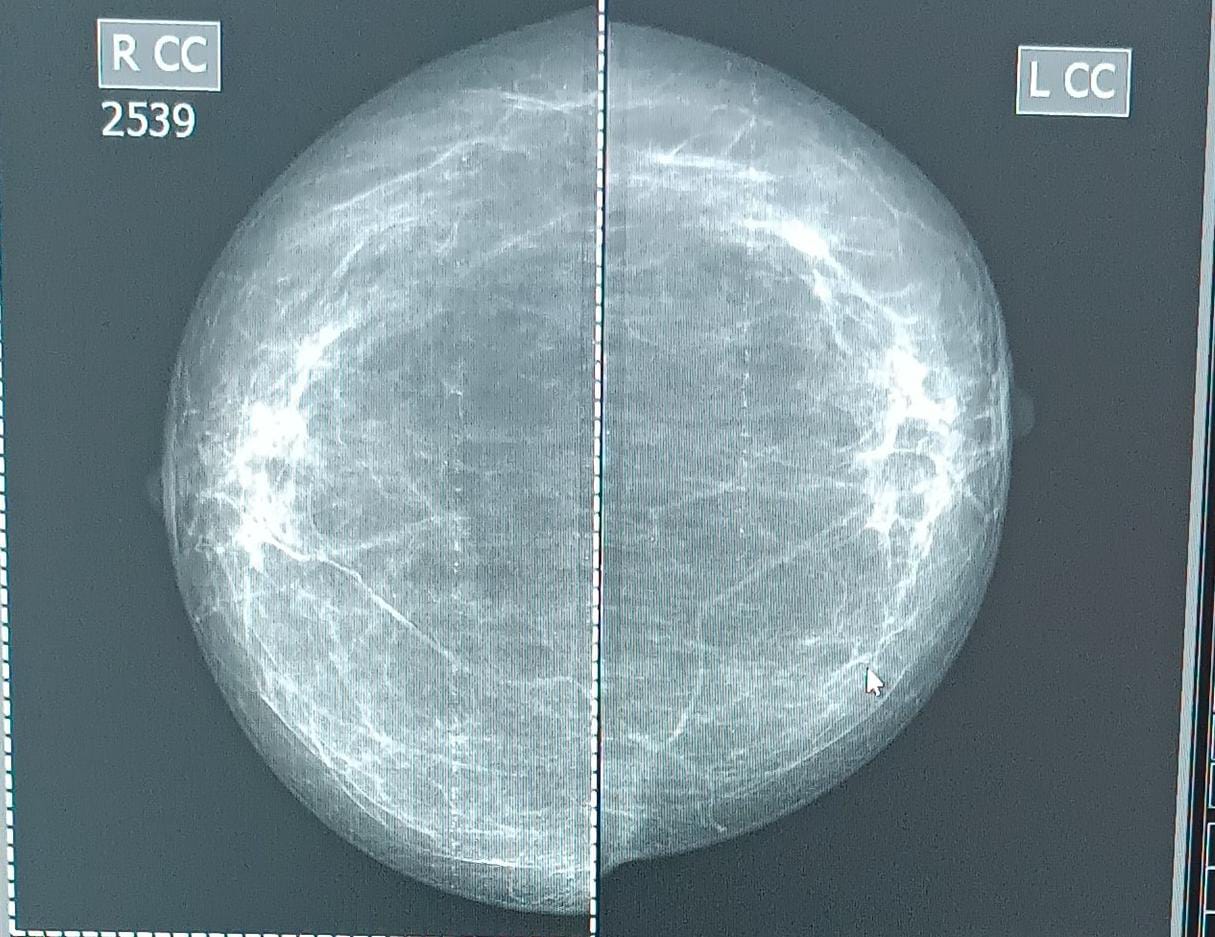

Маммография - рентгеновский метод исследования молочных желез. На сегодняшний день считается одним из самых информативных при диагностике доброкачественных и злокачественных новообразований. Выявленные новообразования могут быть доброкачественными и злокачественными опухолями, кистями. Таким образом, маммография - метод диагностики и профилактики рака. Это безболезненная и не вызывающая какого-либо дискомфорта процедура, длительность которой не превышает нескольких минут. Опасное заболевание, как рак грудной железы, может развиться не только у женщины, но также и представителя сильного пола. Если у мужчины любого возраста неестественно увеличилась одна или обе молочные железы, они стали болезненными, в них появились уплотнения или произошли какие-то другие изменения, необходима провести рентгенологическое исследование. Маммография - ее многие женщины избегают, якобы, из-за облучения. Да, обследование даёт лучевую нагрузку на организм. Но современные цифровые маммографы выдают такую низкую дозу облучения, что негативно на ваши молочные железы, да и организм в целом, это никак не повлияет. С профилактической целью маммографию молочных желез рекомендуется выполнять ежегодно всем женщинам старше 40 лет. Это связано с изменением гормонального фона, что повышает риск развития онкологических заболеваний.